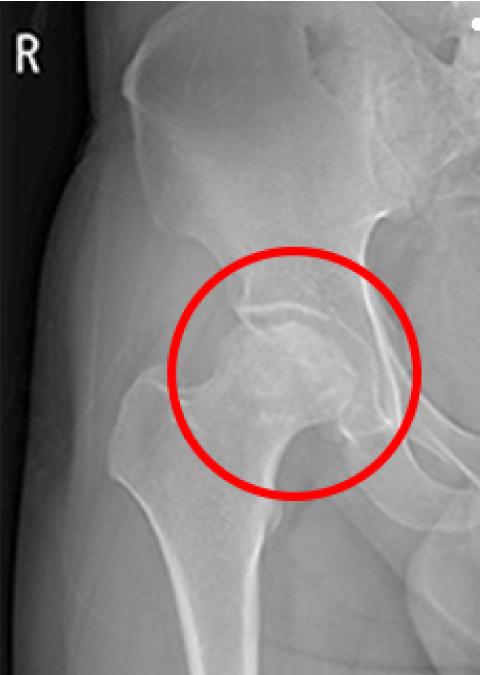

인공관절 수술 전

ㆍ환자 동의를 받은 자료이며, 이미지 사진은 실물과 다를 수 있습니다.

ㆍ2016.09.12(전) 2016.11.22(후)